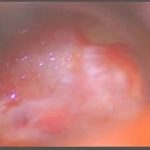

術中写真

摘出 中

摘出 後